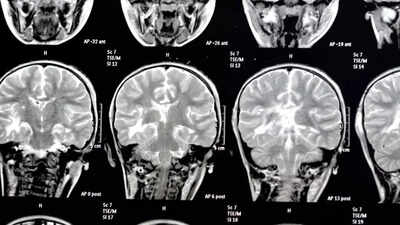

This silent threat is around us. It’s not invisible, but yet overlooked. And the destruction it causes? Brain damage. We are talking about a common health threat that is secretly lurking around us. A new study has revealed that long exposure to this hazard can increase the risk of developing dementia, including Alzheimer’s disease and vascular dementia, conditions which were earlier believed to be mainly linked with lifestyle and genetics. A study led by the researchers at the Medical Research Council (MRC) Epidemiology Unit at the University of Cambridge found that long-term exposure to outdoor air pollution can increase the risk of dementia. The findings are published in The Lancet Planetary Health.Dementia is on the rise worldwide

There are several mechanisms by which air pollution causes dementia. One of the proposed explanations is that it causes inflammation in the brain and oxidative stress, both contributing to the onset and progression of dementia. Air pollution is thought to trigger these processes through direct entry to the brain or via the same mechanisms underlying lung and cardiovascular diseases.“Efforts to reduce exposure to these key pollutants are likely to help reduce the burden of dementia on society. Stricter limits for several pollutants are likely to be necessary, targeting major contributors such as the transport and industry sectors. Given the extent of air pollution, there is an urgent need for regional, national, and international policy interventions to combat air pollution equitably,” joint first author Clare Rogowski, also from the MRC Epidemiology Unit, said.Exposure to air pollutants was linked to a higher risk of Alzheimer’s, but the effect appeared stronger for vascular dementia, which affects about 180,000 people in the UK. However, more research is required on this. “These findings underscore the need for an interdisciplinary approach to dementia prevention. Preventing dementia is not just the responsibility of healthcare: this study strengthens the case that urban planning, transport policy, and environmental regulation all have a significant role to play,” joint first author Dr Christiaan Bredell from the University of Cambridge and North West Anglia NHS Foundation Trust added.